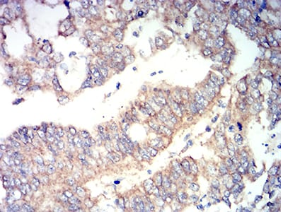

RUNX3 Mouse Monoclonal antibody[7E2B8]

Species Reactivity:    Human

IHC    1/200 - 1/1000